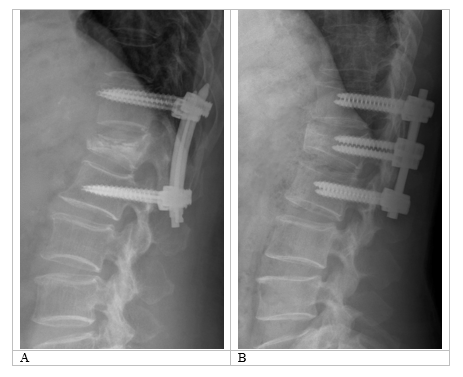

Four transpedicular fixation configurations were modeled for the two vertebrae adjacent to the injured one. These configurations involved either short or long fixation screws passing through the anterior surface of the vertebral body, with or without the placement of two intermediate screws in the T12 vertebra. As an example, Figure 1 shows spondylograms of patients who underwent surgery for a burst fracture of a single vertebra in the thoracolumbar region, treated with short fixation both without and with intermediate screws.

Figure 1 Examples of spondylograms of patients following surgical treatment for burst fractures of the thoracolumbar region. (А) Short fixation without intermediate screws; (B) Short fixation with intermediate screws.